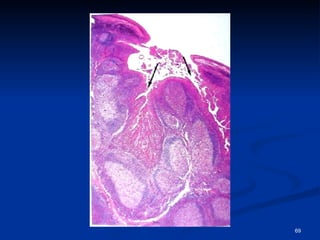

Tonsilas palatinas Bilaterais - localizadas no limite entre a cavidade oral e a orofaringe, entre as pregas palatoglossal e palatofaríngea Recoberta por epitélio estratificado pavimentoso não-queratinizado, que forma 10 a 12 criptas profundas. que se invaginam no parênquima da tonsila - contém células epiteliais descamadas, leucócitos mortos, bactérias e restos de comida Parênquima da tonsila é constituído por numerosos nódulos linfóides, muitos com centros germinativos, indicativos de formação de células B

Tonsilas palatinas Bilaterais- localizadas no limite entre a cavidade oral e a orofaringe, entre as pregas palatoglossal e palatofaríngea Recoberta por epitélio estratificado pavimentoso não-queratinizado, que forma 10 a 12 criptas profundas. que se invaginam no parênquima da tonsila - contém células epiteliais descamadas, leucócitos mortos, bactérias e restos de comida Parênquima da tonsila é constituído por numerosos nódulos linfóides, muitos com centros germinativos, indicativos de formação de células B